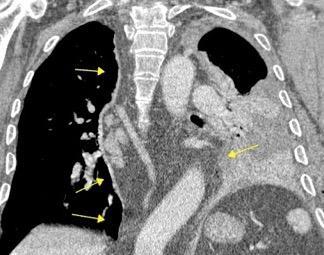

Ganglios retroperitoneales (flechas negras)

germinales del testículo izquierdo Nódulos pulmonares múltiples. (flechas verdes). Ganglios paratraqueales. (flechas amarillas). Dudoso ensanchamiento retrocrural (flechas negras)

Panda A et al. “Straddling Across Boundaries”. Thoracoabdominal Lesions: Spectrum and Pattern Approach. Curr Probl Diagn Radiol, 2015